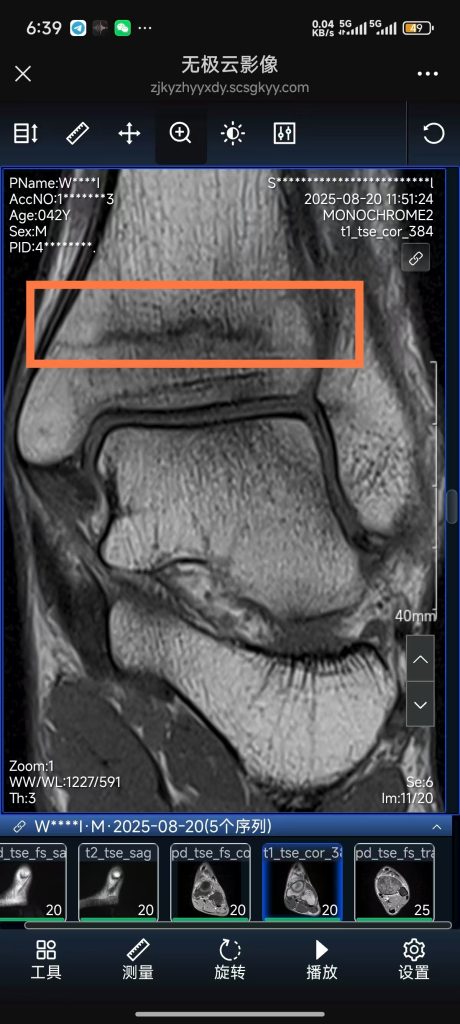

日志 真断了 2025年 8月 22日 / 神特么居然是应力性骨折。这下惨了。估计是那天强行冲400km太疲劳了。导致骨头来不及恢复。那天那个30km的盘山公路太磨人了。 哎。。。。。。受够了。 这下要休息3-6个月了。 祝我的骨折早点痊愈吧。 这个胫骨远端不太好恢复,因为周围血管少。哎 我年纪也不小了。 希望能赶上重马。